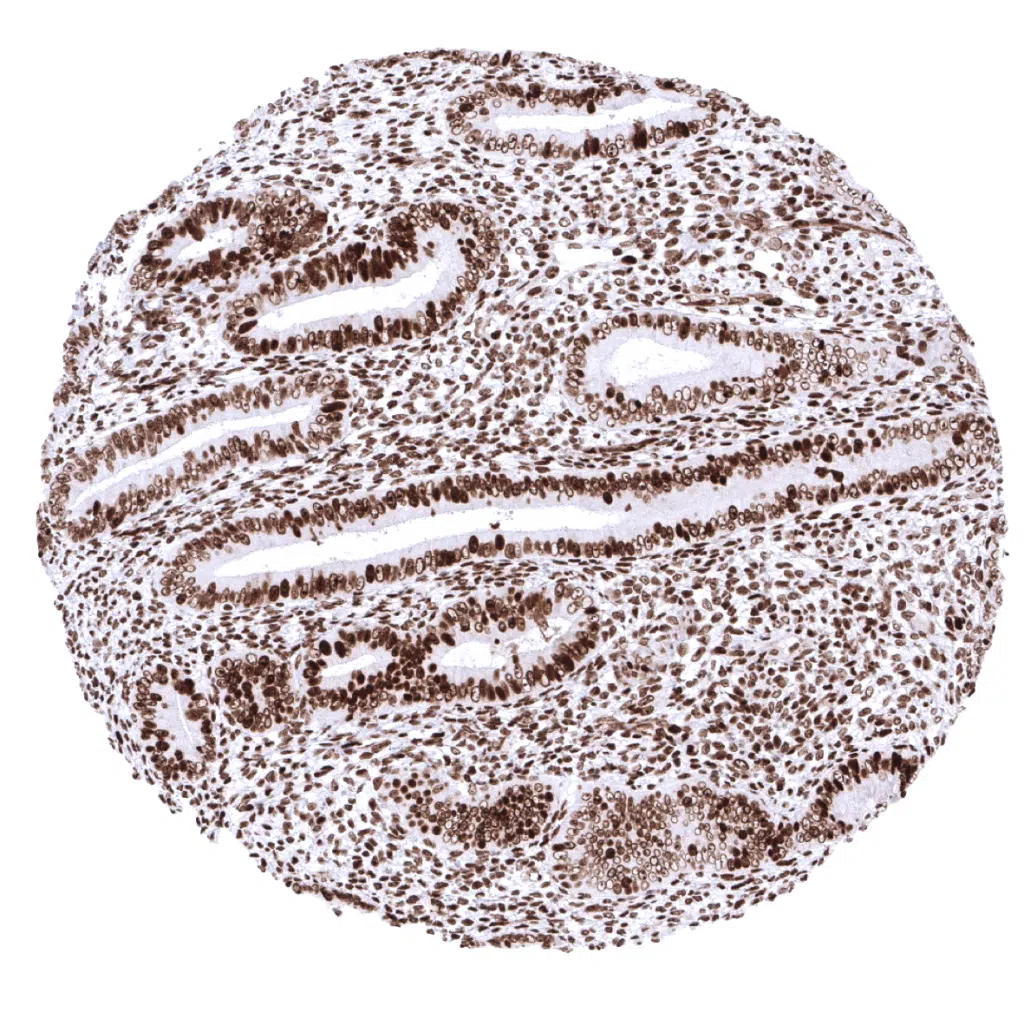

Colon, mucosa – In the colon epithelium, the MSH2 staining intensity decreases from the bottom to the top of the crypts.